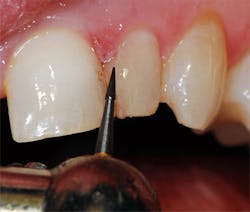

A local anesthetic (4% Septocaine with 1:100,000 epi, Septodont) was administered. The defective composite was removed with a 330 carbide bur (SS White) in a high-speed handpiece with water. Recurrent decay was noted at the gingival margin and was removed to reveal sound, intact dentin. An old cavity liner had been placed under the defective composite, and a small portion of this was left intact over the center of the preparation. The cavity liner was intact and not displaceable with an explorer (figure 2). To minimize postoperative sensitivity, a selective-etch technique was used. A 37% etching gel was applied to the enamel areas of the tooth for 20 seconds, then rinsed and dried. Cotton roll isolation was placed.

Figure 2: The old composite was removed with a carbide bur, and the enamel margins were roughened with a diamond bur in a high-speed handpiece.